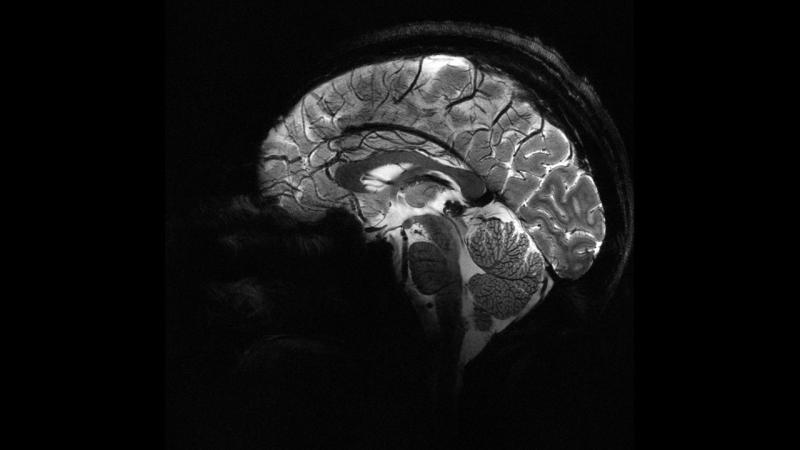

Epilepsi tedavisinde en kritik aşama doğru tanı koymak. Çoğu zaman EEG ve MRI gibi görüntüleme yöntemleri kullanılsa da bazı lezyonlar gözden kaçabiliyor. Bu noktada yapay zeka, yüksek çözünürlüklü taramalardan elde edilen binlerce veriyi saniyeler içinde analiz ederek doktorlara ek bir bakış açısı sunuyor.

Epilepsili çocuklarda görülen bazı lezyonlar, klasik görüntüleme yöntemlerinde “normal” görünebiliyor. Bu durum, yanlış tanı veya yetersiz tedaviye yol açabiliyor. Yapay zeka algoritmaları, bu “gizli lezyonları” tespit ederek çocukların daha erken ve doğru tedavi almasını sağlayabiliyor.

Örneğin, MRI’da temiz görünen bir beyin bölgesinde aslında mikroskobik düzeyde farklılıklar bulunabiliyor. Yapay zeka, bu küçük farklılıkları istatistiksel karşılaştırmalarla ortaya çıkarıyor.

Yapay zeka, binlerce beyin görüntüsünü dakikalar içinde tarayabiliyor. Bu, klasik yöntemlere göre ciddi bir zaman tasarrufu anlamına geliyor.

2025 yılı itibariyle yapılan klinik testlerde, yapay zekanın epilepsili çocuklarda doktorların fark etmediği lezyonları %30 daha fazla yakalayabildiği bildirildi. Bu oran, gelecekte epilepsi tedavisinde yapay zekanın standart bir araç haline gelebileceğini gösteriyor.